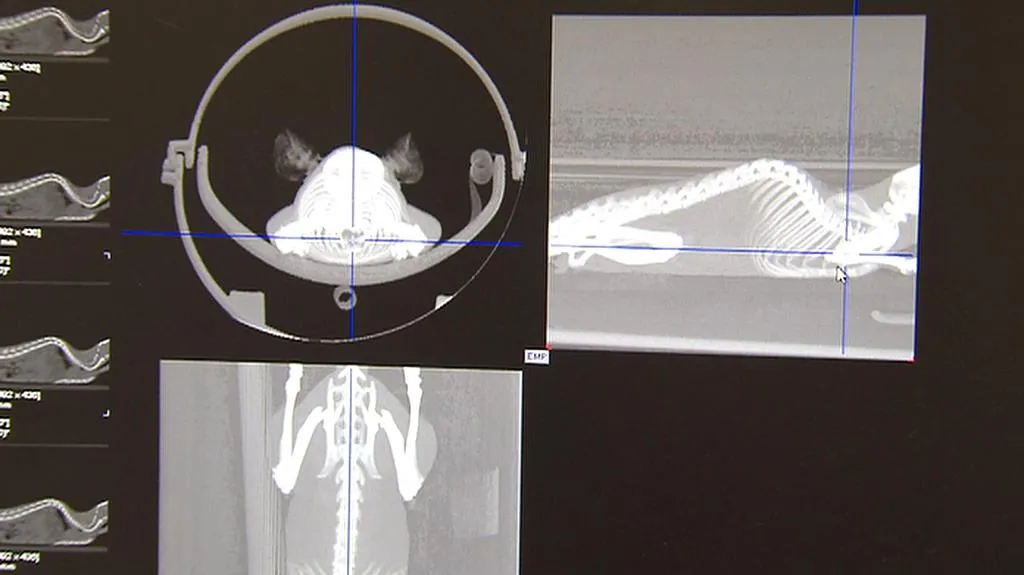

Podle záření tak vědci třeba určí, které tkáně spotřebovávají víc cukrů, kde je tkáň deformovaná nebo špatně roste či kde je tkáň se zánětem. Přístroj o velikosti zhruba 80 krát 80 centimetrů jim umožňuje sledovat i po několik měsíců vývoj patologických znaků. Zvenčí má zabudováno jakési korýtko, kam se hlodavec v lehké narkóze umístí. V zařízení je pak podroben všem potřebným vyšetřením, může to trvat pět minut až dvě hodiny.

Obraz z tomografu, který prosvětluje uspané hlodavce, má až tisíckrát lepší rozlišení oproti přístrojům pro lidi. Experimentálním genetikům metoda usnadní zjišťování genů, které stojí v pozadí nemocí.